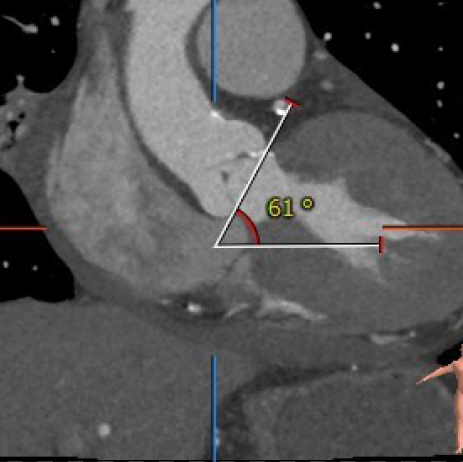

4. 针对甲状腺功能减低可能对心律影响问题,术中采用cusp overlap view和coplanar view联合定位瓣膜,避免瓣膜植入过深造成传导阻滞。

7. 针对横位心问题,采用沛嘉三代瓣膜,干瓣预装瓣膜,过弯能力强,同时术中输送球囊及瓣膜时需轻柔操作,确保导丝和器械的同轴性。

综合上述情况,拟从右侧股动脉穿刺入路,采用20mm球囊进行预扩张,优先准备TaurusNXT AV23预装载系统(备AV26)。